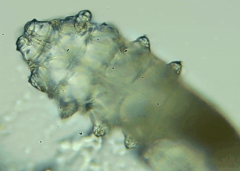

人體上寄生著兩種蠕形螨,分別是毛囊蠕形螨和皮脂蠕形螨,他們通常呈乳白色、半透明的細(xì)長(zhǎng)狀,擁有四對(duì)腳,以睫毛囊上皮細(xì)胞、腺體內(nèi)脂質(zhì)為食物,因此主要寄生在面部、眼睛、頭皮等地方,其中寄生在眼睛里的蠕形螨主要活動(dòng)在睫毛毛囊、睫毛皮脂腺,以及瞼板腺里。

蠕形螨完全長(zhǎng)大也只有0.1-0.2毫米,因此肉眼難以看到它們,只有在電子顯微鏡下我們才能看到睫毛根部的一只只蠕形螨。這些螨蟲(chóng)每天都很活躍,且繁殖速度極快,完成一代生活史僅需大概15天。

螨蟲(chóng)鏡檢:

在檢查的時(shí)候,醫(yī)生要在每個(gè)眼瞼上拔出幾根比較典型的睫毛,然后放在光學(xué)顯微鏡下,尋找有沒(méi)有螨蟲(chóng)。

如果任意一個(gè)眼瞼上發(fā)現(xiàn)了三只及以上的螨蟲(chóng),再加上如果你有眼睛的局部癥狀,就需要進(jìn)行相應(yīng)的治療了。